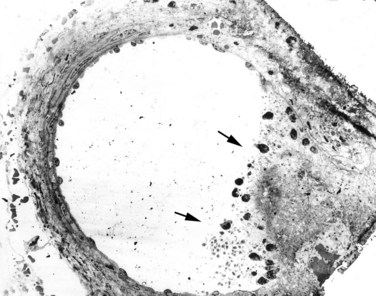

In porcine subjects, the preferred animal model for studying acute renal injury, SWL traumatizes vessels ranging in size from the glomerular and cortical capillaries and vasa recta, to the larger arcuate and intralobular vessels. The resulting hemorrhagic lesion generally extends from cortex to medulla and comprises torn blood vessels with platelet aggregation and red blood cells in the interstitial space (Figs. 48-25 and 48-26 on the Expert Consult website

). Affected renal corpuscles typically show breaks in the Bowman capsule, blood in the urinary space, and damage to the podocytes and mesangial cells (Fig. 48–27 on the Expert Consult website

Figure 48–25 Light micrographs of an acute shockwave lithotripsy (SWL)-induced lesion at F2 (A) and subsequent chronic changes at a similar site 3 months after SWL treatment (B). Each pig kidney was treated with 2000 shockwaves at 24 kV by an unmodified Dornier HM3 lithotripter. The acute lesion is characterized by numerous sites of hemorrhage (arrows) that extend from an individual renal papilla (asterisk) to the outer cortex of the kidney. Note a subcapsular hematoma (double arrows, A). The tissue section in B is similar in location to that seen in A but is shown at 3 months after SWL. A rectangle outlines the site of F2. Within that region there is complete loss of the renal papilla (the asterisk indicates where it should be), and only scar tissue is found in the adjacent cortical tissue (arrow).

Figure 48–26 Low-magnification transmission electron micrograph demonstrating injury to a medium-sized artery located within F2 of a pig treated with 2000 shockwaves at 24 kV. The shockwave-induced injury to the right side of this vessel resulted in a rupture site that permitted extravasation of blood into the nearby interstitium. The site of injury in the vessel wall is plugged with a clot (arrows).